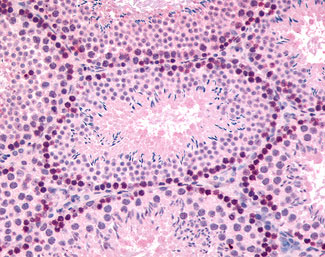

Anti-GLI2 antibody IHC of mouse, testis.